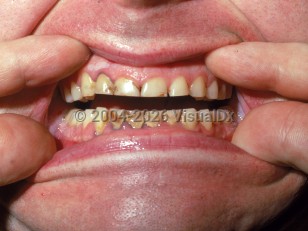

Lead poisoningLead poisoning